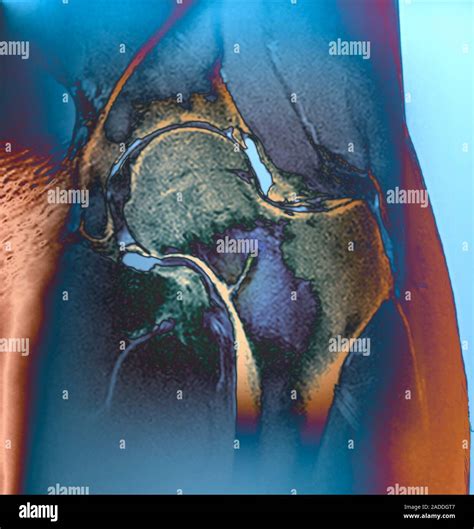

• MRI (Magnetic Resonance Imaging): This is the gold standard for diagnosing a stress fracture. It is highly sensitive and can detect bone marrow edema, which is the earliest sign of stress-related bone injury.